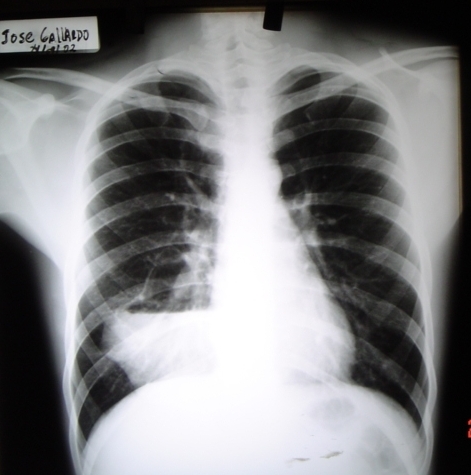

- <div style=fiogf49gjkf0dFig.1-2. Radiografía Posteroanterior y Lateral dónde se evidencia imagen radioopaca de bordes bien definidos con nivel líquido en su interior localizada en base posterior derecha.">

Fig.1-2. Radiografía Posteroanterior y Lateral dónde se evidencia imagen radioopaca de bordes bien definidos con nivel líquido en su interior localizada en base posterior derecha.